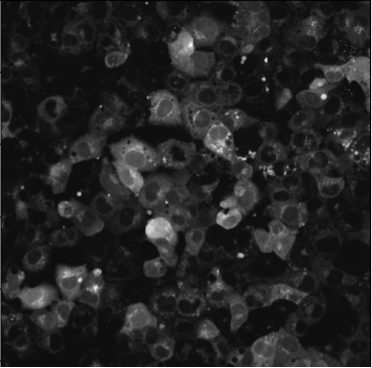

Data employed in this study consist of a live-cell imaging dataset comprising video recordings acquired from CLSM experiments on HL-1 CM networks, which have been widely characterised in previous studies [10, 7, 12, 18]. To visualise intracellular signals, HL-1 networks were loaded with Fluo-3 AM, a fluorescent reporter used extensively in biological imaging of signalling dynamics. Changes in Fluo-3 AM FI, associated with CM contraction, were recorded for at pixel resolution in AVI video format [7, 12]. Each recording produced a multi-temporal frame stack of frames for subsequent processing.

To complement the quantitative analysis of NR-IQA scores and assess whether the chosen image quality metrics effectively correlate with changes in the visual quality of our microscopy images, we conducted a complementary qualitative analysis on an exemplary subset of the HL-1 dataset (N = 18). PIQE, NIQE and BRISQUE were individually sorted in ascending order to identify exemplary images scoring the closest values to the minima, median and maxima identified in Table 2. Results of this analysis are summarised in Figure 3. PIQE assigned the highest values (i.e., P = 79.07 and P = 79.76) to images characterised by high levels of blur (Figure 3c), penalising decreases in image sharpness and losses of fine details over other signs of image quality deterioration, including the high salt and pepper noise and low brightness observed in high and median quality images for PIQE (Figure 3b). Differently, NIQE and BRISQUE were shown to penalise images that were substantially degraded by the specific preprocessing pipeline applied, primarily images belonging to the PDP group, associated with the highest values for all three metrics (Figure 2). Both NIQE and BRISQE were proven sensitive to alterations of the original images, leading to the generation of artefacts introduced by the preprocessing pipeline and previously not observed within the raw frames. Examples of these alterations are visible from the exemplary median quality images reported for the two metrics (Figure 3b). NIQE was also shown to penalise low image contrast, considering images characterised by high foreground-to-background contrast of higher quality than images characterised by low brightness and low illumination variability between cellular and background structures.

Highest quality images identified by the lowest PIQE, NIQE and BRISQUE scores were subjected to the expertise of an experimentalist researcher with extensive experience of working with signals from HL-1 networks, which empirically determined the existence of incongruencies between the perceived quality assigned by each NR-IQA score and the visual quality and usefulness of the image for GT annotation (see Section 6.2). Figure 4 reports the results of this analysis, comparing images identified of High Perceived Quality (HPQ) by PIQE, NIQE and BRISQUE scores (Figure 4a) with images considered to have better perceived quality by the expert. It is worth noticing that, while HPQ images identified by the experimentalist substantially outperform the quality of the best HPQ images identified by PIQE and BRISQUE, we found agreement between the HPQ images identified by NIQE and the ones chosen by the experimentalist, with three out of four images scoring similar NIQE scores to the HPQ images selected by the experimentalist. Oppositely, PIQE and BRISQUE showed incongruencies between the score assigned to the best (Figure 3a) and median quality images (Figure 3b) and the translation of these scores into the effective perceived quality of the images. Therefore, both scores assigned HPQ values to low brigthness images characterised by poor foreground-to-background contrast and extremely impaired visibility of regions of cellular density and most importantly of cellular boundaries, essential to allow the annotations of HL-1 images.

Amongst the six projection methods tested in the study, MIP, QP and SP methods were selected by the experimentalist as the methods yielding HPQ images (Figure 9). The preprocessing-projection combination methods selected were shown to generate images with high foreground-to-background contrast, which, together with high image brightness, facilitates the differentiation of cellular and background material in HL-1 images. These methods were also associated with an increased perceptive visibility and sharpness at cellular boundaries, making cell-to-cell connection more visible and facilitating the experimentalist in the recognition of cellular structures that characterise complex HL-1 networks for downstream GT annotation (as discussed in Section 6.2). Interestingly, CH and GH preprocessing methods in combination in two out of four of these methods, associated with MP and SP projections, and again in their lower value version (i.e., GL and CL) with SP projections and CL alone with QP methods (as shown in Figure 6). Notably, combined CH and GH approaches, preceded or followed by filtering methods, MB, NF and BF amongst the most common, also appear in the best methods combinations identified by PIQE, NIQE and BRISQE scores (see Figure 5). The value of using CLAHE with GF methods and NF techniques has been previously shown in medical imaging datasets [36], but never tested on FM datasets and in combination with projection methods for multi-temporal image fusion.